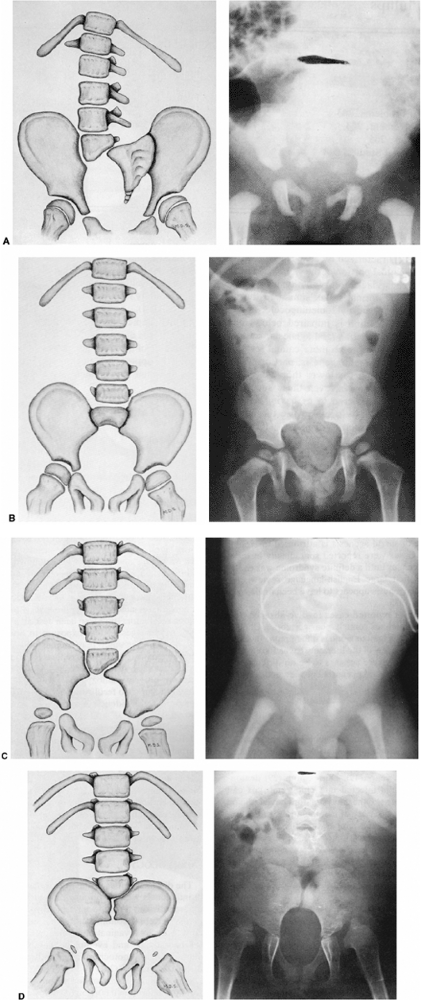

![]() |

Figure 16.11 Two types of lumbar kyphosis: the C-shaped collapsing curve (top) and the S-shaped curve (bottom). (From Loder RT, Shapiro P, Towbin R, et al. Aortic anatomy in children with myelomeningocele and congenital lumbar kyphosis. J Pediatr Orthop 1991;11:31,32,33,34,35, with permission.)

|

categories: a collapsing “C” shaped deformity and a more rigid “S”

shaped deformity (232) (Fig. 16.11).